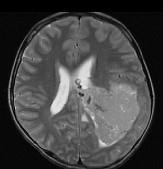

问题 男,8岁,头痛伴呕吐,左侧眼视物不适5天,请根据所提供图像,选择最可能的诊断()

选项 A.(左侧脑室)脑膜瘤 B.(左侧脑室)室管膜瘤 C.(左侧脑室)脉络丛乳头状瘤 D.(左侧脑室)胶质瘤 E.(左侧脑室)少突胶质细胞瘤

答案 C